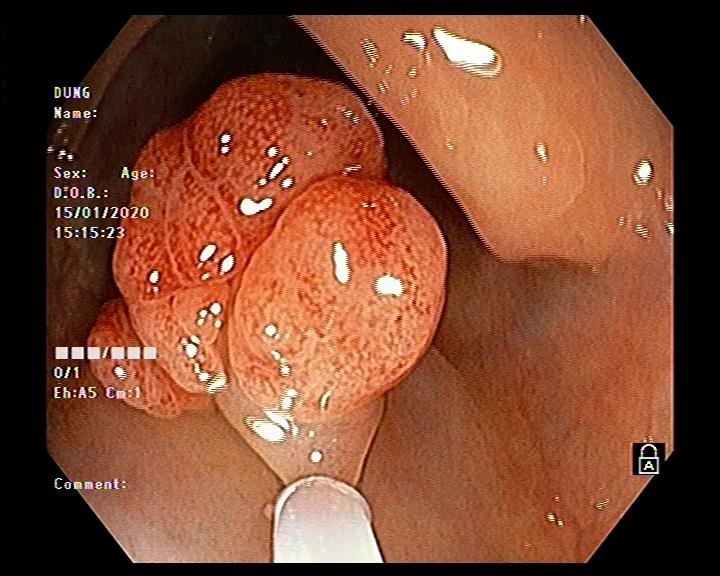

Hình ảnh nội soi đại tràng cắt polyp

Vấn đề đặt ra là với kích thước và tính chất polyp như vậy thì có khả năng polyp được nuôi bằng mạch máu lớn, nếu chỉ cắt đốt bằng phương pháp thông thường thì nguy cơ xuất huyết ồ ạt sẽ rất cao. Do đó bác sĩ nội soi Ths Vũ Thanh Tùng quyết định sử dụng vòng Endoloop để thắt cuống polyp trước khi tiến hành cắt đốt. Thủ thuật diễn ra thuận lợi, nhanh gọn trong vòng 10-15 phút và không xảy ra tai biến dù là polyp này được nuôi bằng mạch máu lớn.

Hình ảnh thắt cuống polyp bằng vòng Endoloop